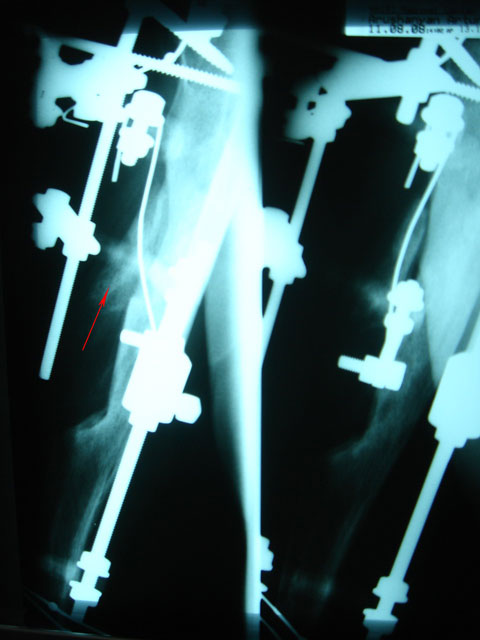

В том то и дело, что инфицирование остется. Я бы применил методику

возмещения инфициированной полости "скользящим отщепом" . Как говорил

Илизаров "инфекция сгорает в огне регенерации" Поэтично, но поверьте это

работает почти безотказно, если конечно больной согласится на очередной

аппарат

Снимки в приложении, удачи

Аршак Мирзоян

Ереванский Центр Реконструкции и

Удлинения Конечностей